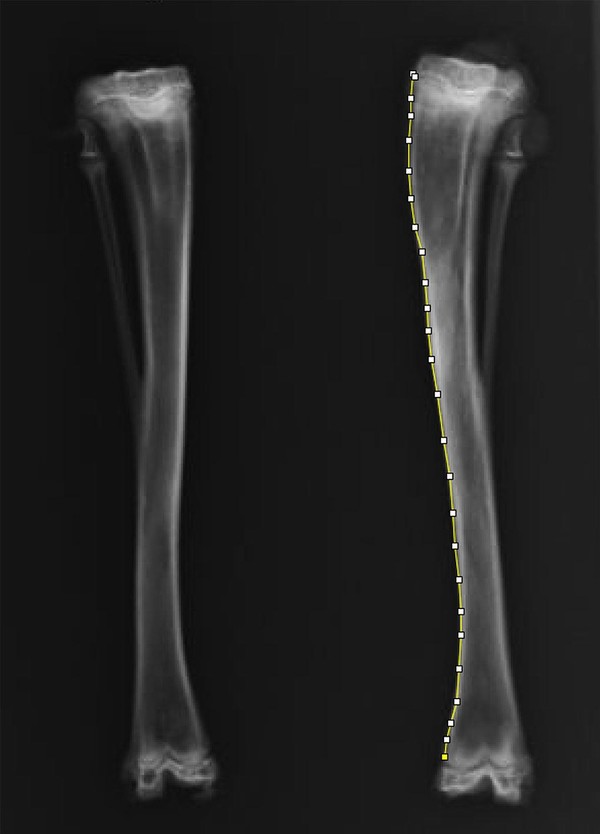

공동 연구팀은 성장기 토끼의 정강이뼈 성장판에서 각각 5mm, 10mm, 15mm 떨어진 위치에 구멍을 만들고, 그 속을 다양한 재료로 채운 뒤 성장 변화를 비교했다. 그 결과 성장판에서 10mm 떨어진 부위에 구멍을 내고 뼈 왁스(bone wax)를 채운 경우, 뼈가 정상보다 더 길게 자라는 과성장과 함께 다리가 바깥쪽으로 휘는 외반 변형이 발생했다. 반면 구멍을 비워두거나 다른 재료를 사용했을 때는 뚜렷한 길이 변화가 나타나지 않았으며 외반 변형만 관됐다.